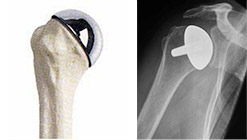

Endoprotesi: in caso di fratture complesse della testa omerale o quando quest’ultima, a causa di una crisi vascolare va in necrosi, viene sostituita solamente la componente omerale, mentre la porzione scapolare non viene protesizzata. La scelta di utilizzare questo impianto dipende anche da fattori legati alla qualità della cartilagine articolare o dell’osso.

Protesi di rivestimento: consiste nella sostituzione della sola superficie articolare della testa omerale con una protesi senza stelo. Il vantaggio maggiore di questa protesi è quella della conservazione ossea ed è una valida alternativa alle protesi di spalla convenzionali. Le protesi di rivestimento sono indicate nei pazienti giovani e attiva, in quanto riduce i processi di usura e quindi il rischio di mobilizzazione protesica. Grazie alla sua natura più conservativa, la protesi di rivestimento può essere, se necessario, facilmente convertita in un secondo tempo in una protesi totale.